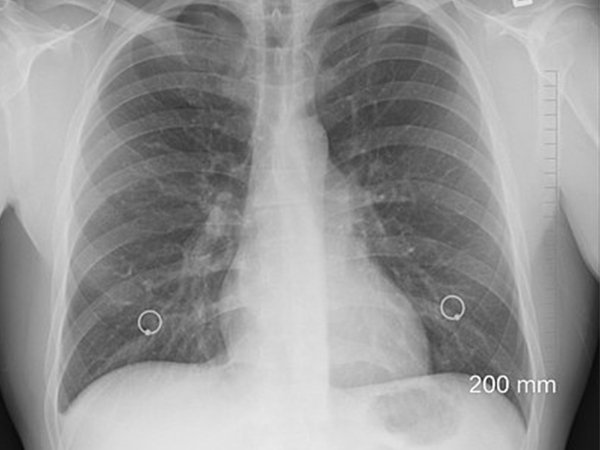

ద్రవం ఎక్కడ పేరుకుపోయిందో చూడటానికి తరచుగా X- రే లేదా EKG తీసుకోబడుతుంది. ఇది అకాల ఊపిరితిత్తుల క్యాన్సర్ సంభావ్యతను తొలగిస్తుంది.